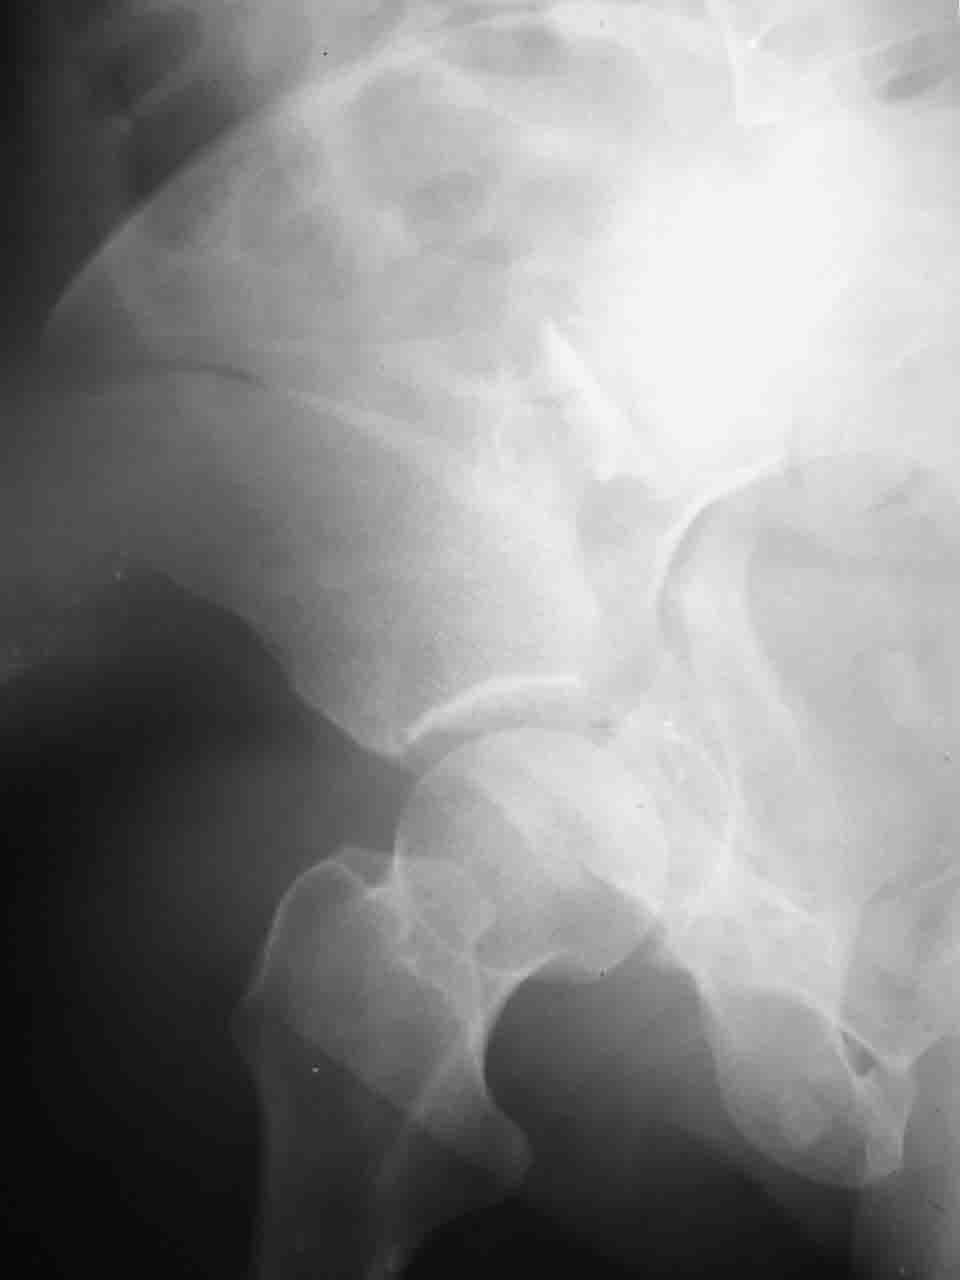

Причиной обращения к сообществу были возникшие непосредственно после операции сомнения и разочарования полученным качеством репозиции: а надо ли было трогать перелом вообще, репозиция передней колонны технически была очень сложна для меня, хотя реконструкции была в той же последовательности, что Д-р А.В.Рунков рекомендовал, в какой-то момент безуспешных манипуляций стал думать о *вторичной конгруэнтности*, которую не так давно обсуждали на

форуме и скелетном вытяжении. С репозицией и фиксацией задней колонны и отдельно задне-верхней стенки впадины проблем не возникло. Послеоп. Рг граммы в приложении. Если возникнут какие-либо дополнения или поправки - был бы признателен.